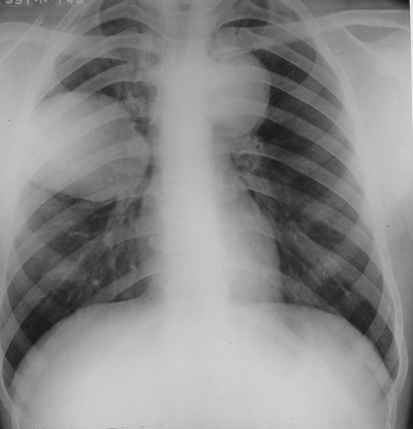

Rx toracică, incidență P-A

DESCRIERE:

pe tot teritoriul pulmonar, bilateral → opacități nodulare multiple de dimensiuni variabile, intensitate medie-mare, omogene, cu contur net

distribuție anarhică

blocuri adenopatice la niv. hilurilor pulmonare

DX: MTS pulmonare hematogene

DD:

hidatidoză - dimensiuni mai mari

bronhopneumonie - contur neregulat, neomogene, distribuție bazală